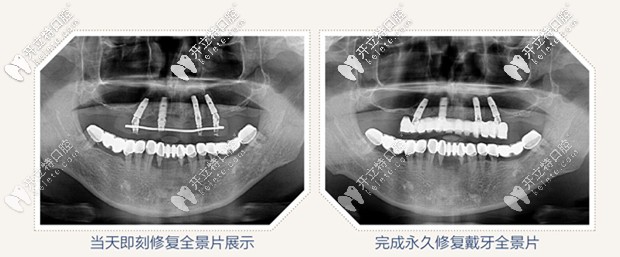

但是經(jīng)過拍片檢查,醫(yī)生說老爸的頜骨情況良好,可以進行即刻種植,為了保證植體植入的準(zhǔn)確性,醫(yī)生給的治療方案是采用數(shù)字化導(dǎo)板微創(chuàng)精準(zhǔn)植入,同時較少了傳統(tǒng)翻瓣手術(shù)的痛苦。

全景片圖示

all on 4即刻種植,只需要植入4顆種植體,就把老爸上半口牙就全給修復(fù)啦,并且是當(dāng)天修復(fù),當(dāng)天戴牙啊,感覺太神奇啦!

All-on-4即刻種植牙效果圖